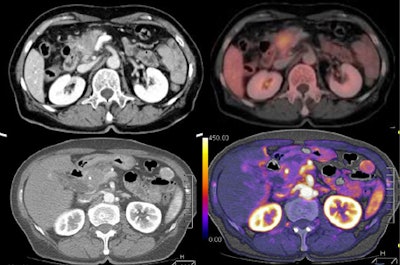

![]()  |

| Tumor and pancreas head are visible on tumor map, with PET image for comparison. All images courtesy of Dr. Sonja Kandel. |